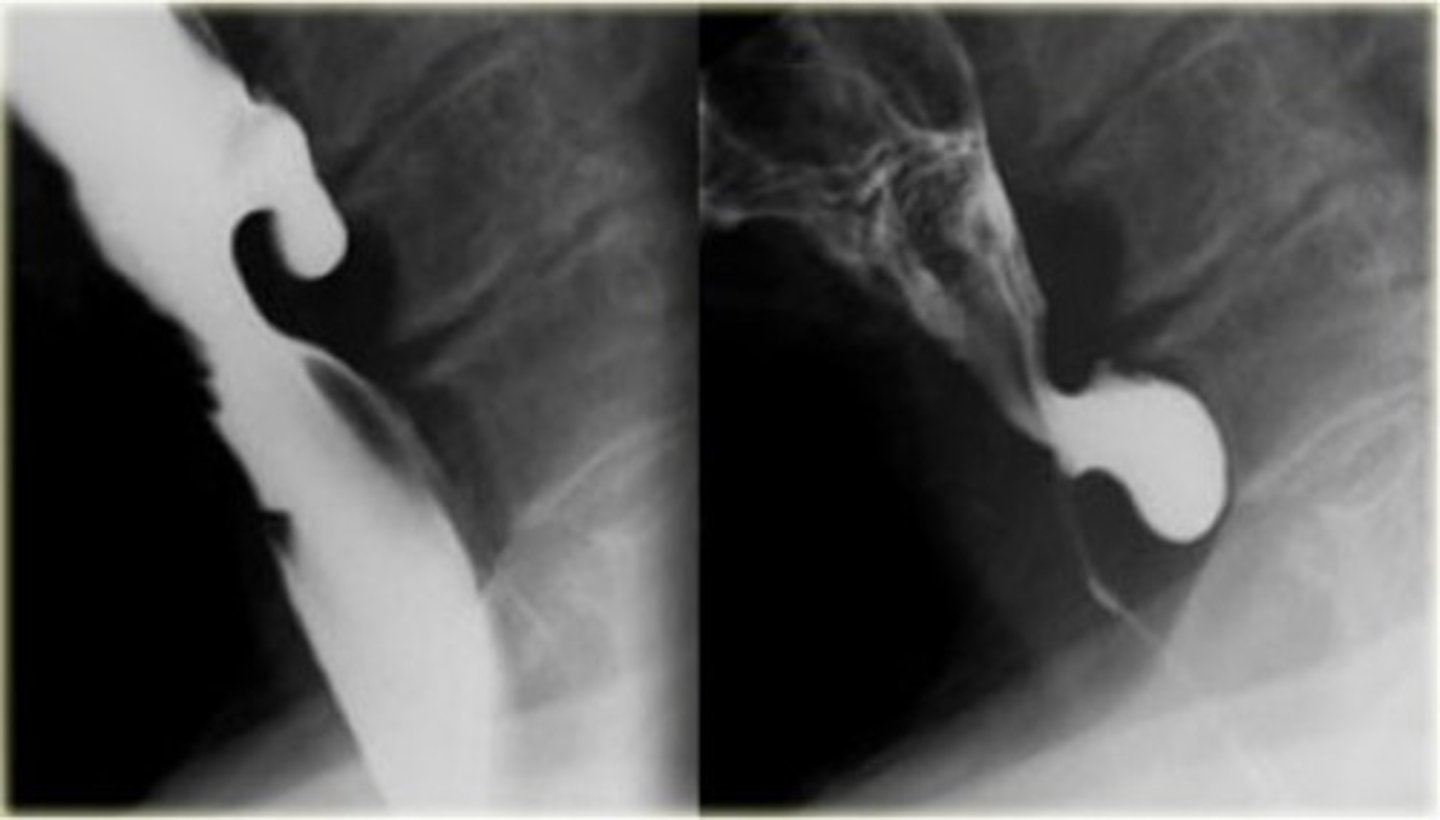

Zenkers diverticulum

Zenkers diverticulum (pic 2)

Zenkers diverticulum (pic 3)